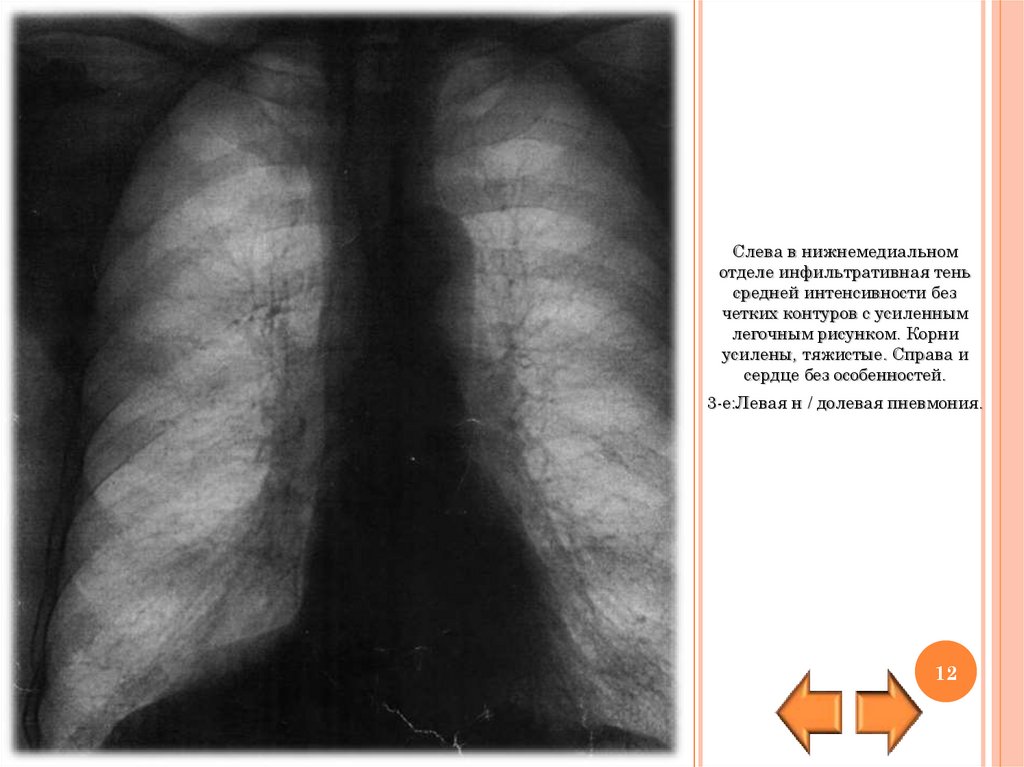

Слева в нижнемедиальном

отделе инфильтративная тень

средней интенсивности без

четких контуров с усиленным

легочным рисунком. Корни

усилены, тяжистые. Справа и

сердце без особенностей.

3-е:Левая н / долевая пневмония.